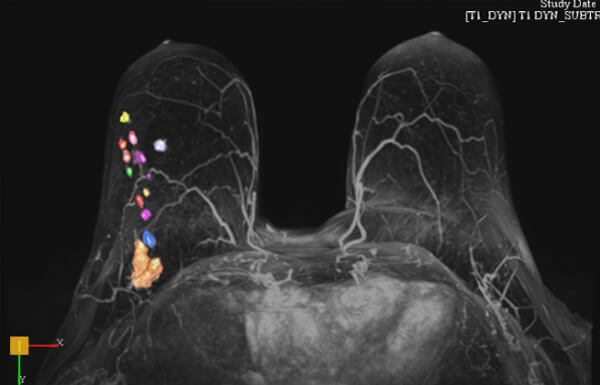

- Εφαρμόζεται στο τμήμα μας από εξειδικευμένους ιατρούς*, με τη χρήση ειδικών τεχνικών πολυπαραμετρικής μελέτης και μετεπεξεργασία δεδομένων σε σύστημα CAD (computer aided diagnosis)

- Επεξεργασία των δεδομένων σε σύστημα CAD

- Προσδιορίζει με μεγάλη ακρίβεια την έκταση του καρκίνου πριν από το χειρουργείο, ώστε ο χειρουργός μαστού να επιλέξει την κατάλληλη θεραπευτική προσέγγιση (ογκεκτομή ή μαστεκτομή, προεγχειρητική χημειοθεραπεία). Σε σύγκριση με τη μαστογραφία και το υπερηχογράφημα, αξιολογεί με πολύ μεγαλύτερη ακρίβεια το μέγεθος του καρκίνου. Σε περιπτώσεις που ο καρκίνος έχει μεγάλη έκταση, μπορεί η γυναίκα να χρειαστεί να υποβληθεί σε μαστεκτομή ή σε χημειοθεραπεία πριν από τη χειρουργική επέμβαση. Αντίθετα, εάν ο όγκος είναι μικρός, μπορεί η γυναίκα να υποβληθεί σε ογκεκτομή και να διατηρήσει τον μαστό της. Τέλος, προσδιορίζοντας με ακρίβεια το μέγεθος του καρκίνου, επιτυγχάνεται ολική αφαίρεση του όγκου σε μία χειρουργική επέμβαση και αποφεύγεται στις περισσότερες περιπτώσεις μια δεύτερη επέμβαση (επανεκτομή).

- Αξιολογεί ταυτόχρονα τον άλλο μαστό (σταδιοποίηση)